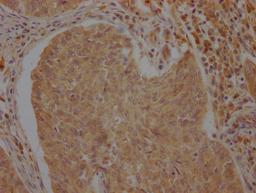

IHC image of CSB-PA002277LA01HU diluted at 1:100 and staining in paraffin-embedded human cervical cancer performed on a Leica BondTM system. After dewaxing and hydration, antigen retrieval was mediated by high pressure in a citrate buffer (pH 6.0). Section was blocked with 10% normal goat serum 30min at RT. Then primary antibody (1% BSA) was incubated at 4°C overnight. The primary is detected by a Goat anti-rabbit polymer IgG labeled by HRP and visualized using 0.05% DAB.